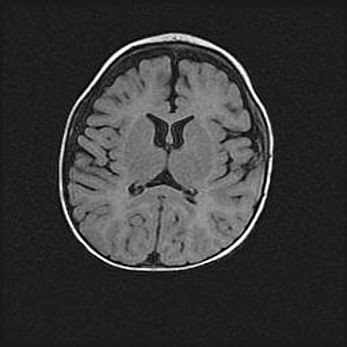

Лейкомаляция с кистозно-глиозной дегенерацией головного мозга.

Возраст: 2 месяца 25 дней

Вес: 6400 г

Окружность головы: 40 см

Срок гестации: 41 неделя

Лейкомаляцию относят к ишемически-гипоксическим повреждениям головного мозга, диагностируемым у новорожденных. При лейкомаляции в головном мозге обнаруживают очаги некроза, возникшие после тяжелой гипоксии и нарушения кровотока. В процессе морфогенеза очаги проходят три стадии: 1) развития некроза, 2) резорбции и 3) формирования глиозного рубца или кисты. Перивентрикулярная лейкомаляция (ПЛ) встречается примерно в 12% случаев среди новорожденных, обычно – у недоношенных детей, причем, частота ее зависит от массы, с которой младенец появился на свет. Наибольшее число малышей страдает лейкомаляцией, если масса при рождении 1500-2500 г.